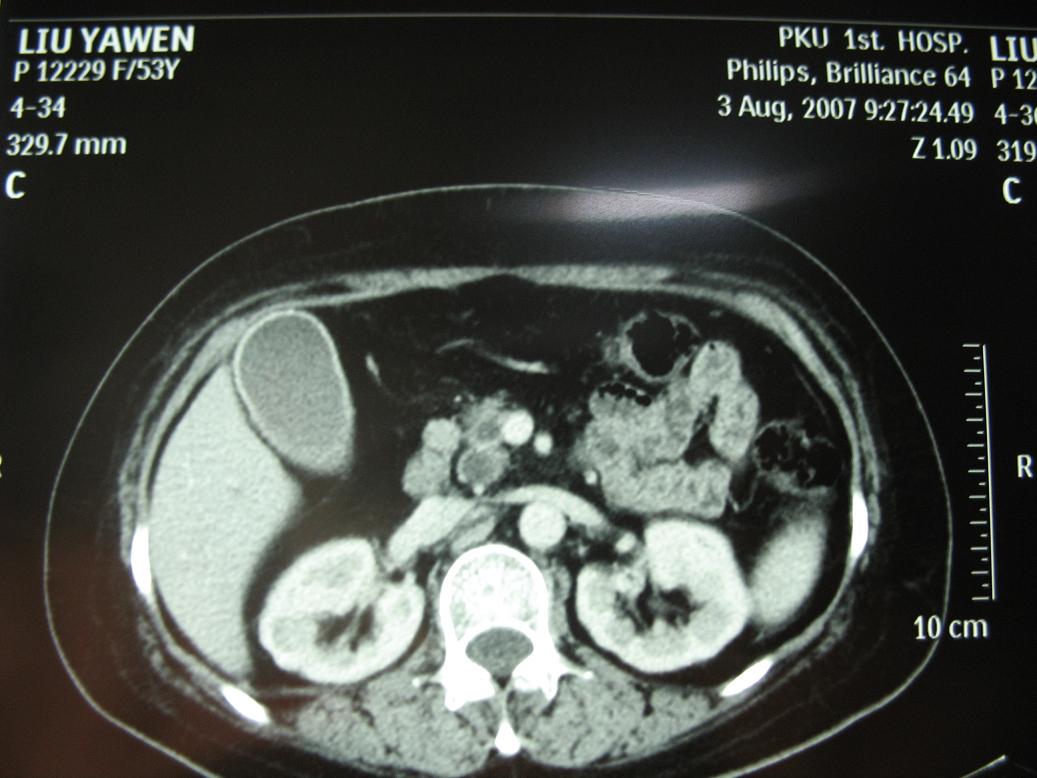

标题: CT17151:女 53岁 腹痛数月余 轻微黄疸 [打印本页]

女 53岁 腹痛数月余 轻微黄疸

1)考虑胰头癌。2)胆囊炎。

壶腹周围占位(钩突ca?)

胰腺钩突mt

支持胰腺钩突ca伴胆系梗阻,胆囊炎

考虑 胰头癌可能性大。